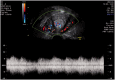

Ultrasound assessment of the postpartum uterus has a significant role to play in the evaluation of a large proportion of symptomatic puerperal women. Often the imaging modality of choice for excluding retained placental tissue, correct application of postpartum ultrasound could enable more accurate identification of women requiring surgical intervention, with consequent reduction in patient morbidity and clinical workload. This article aims to review the current understanding and application of ultrasound in the puerperium and evaluate the current evidence investigating the physiological and pathological findings of the postpartum uterus and its contents.